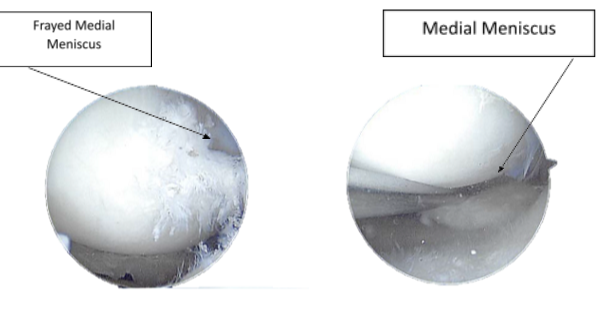

X-ray and MRI were presented in the office. Found vertical tear at the free edge margin of the posterior horn medial meniscus, with mild undersurface/free edge fraying of the body segment. Mild medial femorotibial compartment chondral loss. Mild patellofemoral compartment chondral wear, preferentially over the medial aspect of the compartment.

A probe was introduced. The medial meniscus tear was seen going through the body and the posterior horn up to the root. Shaver was introduced and the margins were cleaned. Upbiter and straight biter were used to remove the degenerated meniscus along the inside edge of the medial meniscus. The scope was moved to the intercondylar notch where an ACL was found to be intact with degeneration.

The scope was moved to the patellofemoral joint again where OA grade 3 to grade 4 lesion was found on the medial tibiofemoral condyle in the appropriate region. It was cleaned using an upbiter and shaver. The knee was reexamined and the medial meniscus was further debrided.